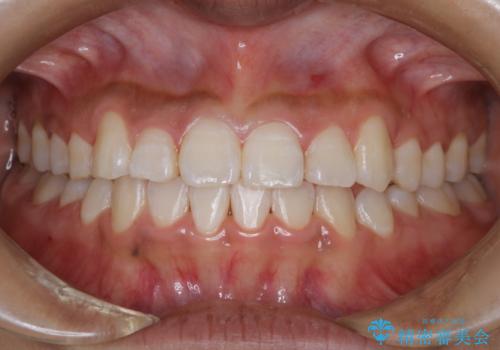

[ 前歯のねじれ・がたつき ] マウスピース矯正

![[ 前歯のねじれ・がたつき ] マウスピース矯正の症例 治療前](https://seimitsushinbi.jp/wp/wp-content/uploads/2024/02/4007c6479f6bce11863dcdd32ed5e39b-500x350.jpg?v=1708502552)

![[ 前歯のねじれ・がたつき ] マウスピース矯正の症例 治療後](https://seimitsushinbi.jp/wp/wp-content/uploads/2024/02/e7a01485e4f4dd0da04705fde4cc34cc-500x350.jpg?v=1708502585)